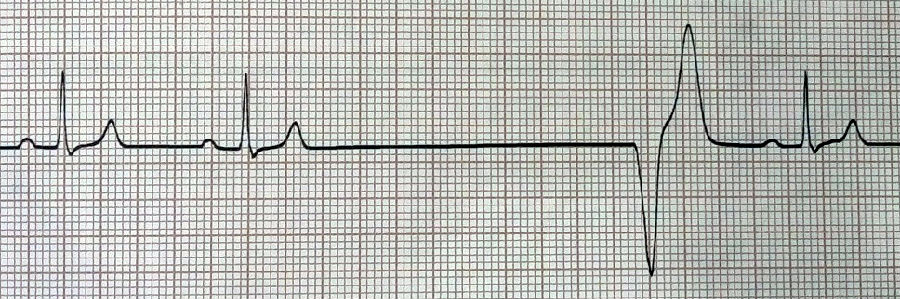

室性逸搏:室性逸搏的关键在“逸”字上,由于窦房结等心室以上太过安逸不干活,心室被迫自己发出电冲动激励自己干活,产生室性逸搏。在心电图上表现就是在经历一个较长的间歇后,心室发出一个电冲动,将心室激动起来,形成室性逸搏,具体如下图所示。

图5

图6